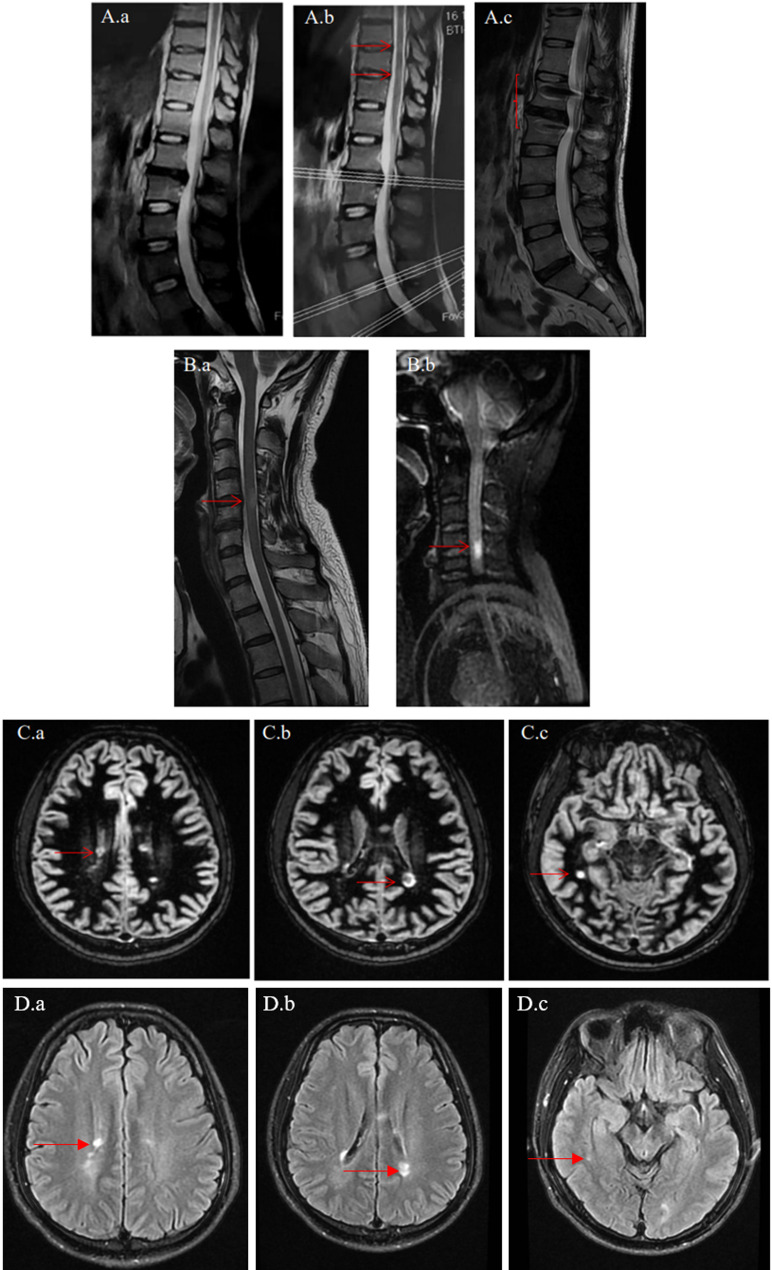

Use of MRI-double inversion recovery sequence for early diagnosis of multiple sclerosis: case series.